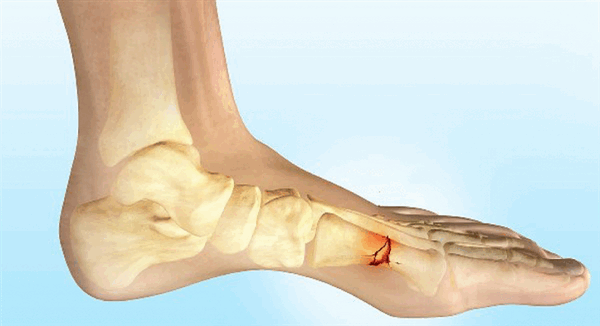

г) Патология. Общая характеристика:

• Этиология:

о Размозжение, тупая травма, сдвигающее или скручивающее усилие, длительная повышенная нагрузка

о Стресс-переломы чаще встречаются у бегунов

о Стресс-перелом основания 2-й плюсневой кости встречается у артистов балета о 5-я плюсневая кость:

- Отрывной перелом бугристости: внутренняя ротация стопы, находящейся в положении подошвенного сгибания; тянущее усилие латеральной части подошвенного апоневроза + короткой малоберцовой мышцы

- Перелом Джонса: избыточное отведение стопы, находящейся в положении подошвенного сгибания

- Стресс-перелом проксимальной части диафиза: повторяющаяся травматизация при беге, танцах